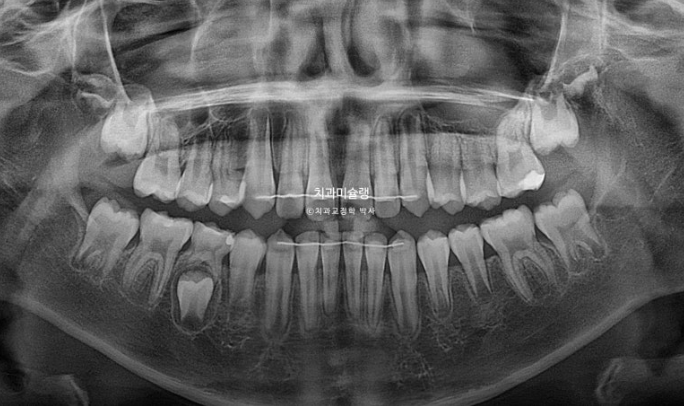

엑스레이 비교를 해보면 이러합니다.

치아 뿌리가 잘 자라고 있습니다.

치근평행도는 좋습니다.